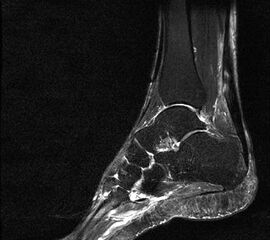

Hier befindet sich ca. 3-5 cm proximal des Tuber calcanei ein als „kritische Zone“ benannter Bezirk, der durch eine ungünstige arterielle Blutzufuhr gekennzeichnet ist (letzte Wiese). Hier finden sich häufig spindelförmige Schwellungen, die bei MRT-Diagnostik nicht selten partielle Nekrosen und Partialrupturen der Achillessehne aufweisen (Abb. 14).

Unabhängig davon können insbesondere chronische Insertionstendinosen der Achillessehne von Partialrupturen (Abb. 15) und erosiven Läsionen des dorsalen Fersenbeines begleitet sein.

Die sonographische Diagnostik eignet sich primär zur Erkennung schmerzhafter Prozesse im Verlauf der Achillessehne und kann bei Bedarf durch Röntgen bzw. MRT ergänzt werden. Besonders bei längeren Verläufen und kräftigen spindelförmigen Schwellungen (>9mm, Normwert <5mm) im Bereich der kritischen Zone sollte ein MRT zum Ausschluss von Nekrosezonen und Partialrupturen vor Therapiebeginn veranlasst werden. Die sonographisch leicht zu erfassende Veränderung der Sehnendicke im mittleren Sehnenanteil ist ein guter Indikator für die Schwere der Erkrankung und die Beurteilung des Behandlungsverlaufes. Die sichtbaren Veränderungen am distalen knöchernen Ansatz der Sehne sind diskreter.

Insbesondere bei größeren Partialrupturen (Abb. 14) sollten operative Verfahren erörtert werden. Kleinere Partialrupturen sind der ESWT gut zugänglich, wie die beiden nachfolgenden Beispiele zeigen: